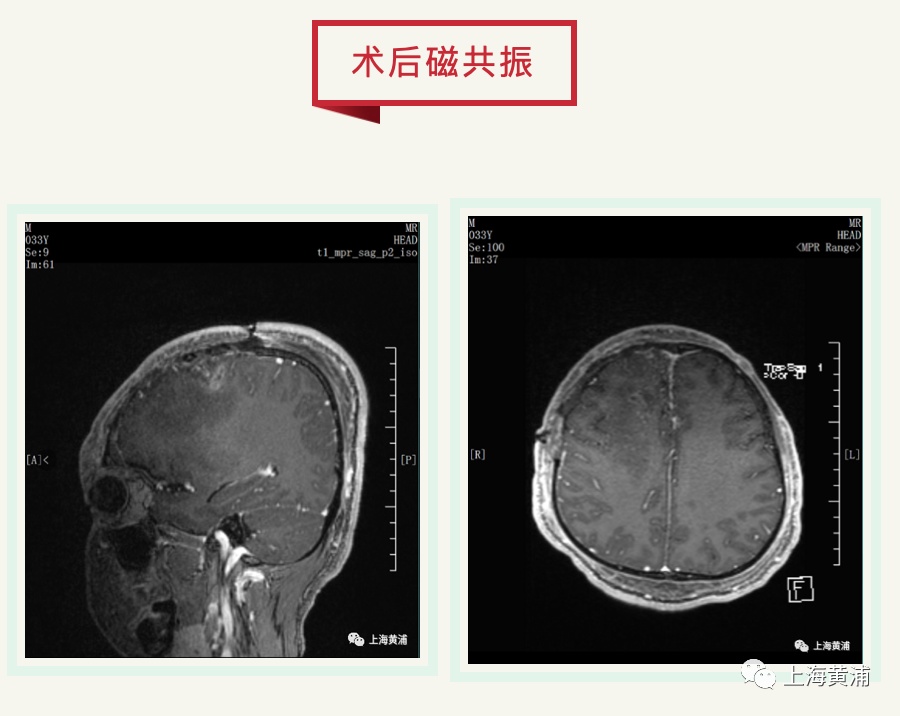

都说神经外科医生是“刀尖上的舞者”,但三层手套之下还要在显微镜下精细操作实属不易。卞留贯、孙青芳主任先后上阵主刀,尽管肿瘤血供丰富,术区渗血明显,但主任们不慌不乱,肿瘤得以彻底切除。6个小时很短,短的只有一瞬;6个小时也很漫长,那是决定患者一生的时长……终于,这些闪耀着人性光辉、医者大爱的孜孜不倦的身影,用精湛的医术与实际行动完美诠释了“广博慈爱、追求卓越”的瑞金精神。

术后,患者安全转运至ICU继续治疗,党委副书记、院长陆勇和副院长胡俊峰早早在隔离区外等候,慰问参加手术的医务人员并了解病情,帮助解决后续治疗存在的困难。第二天,患者清醒拔管,肢体活动自如,对答流畅,大家如释重负,孙主任也终于笑逐颜开。此刻,医护人员们真切体会到“更喜岷山千里雪,三军过后尽开颜”的喜悦。